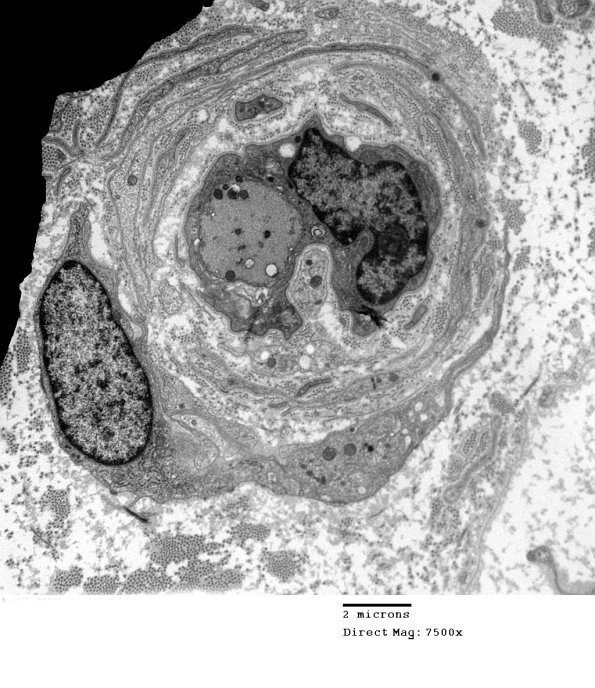

This axon is demyelinated with evidence of prior episodes of demyelination and remyelination in the form of an onion-bulb. (electron micrograph)